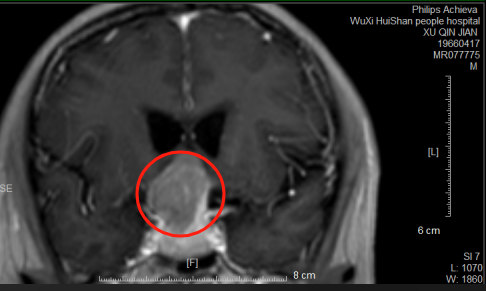

林先生(化名)长期受到垂体瘤困扰,视神经持续受到压迫,因此单眼失明、出现听力障碍,生活中遇到很多困难。

带着希望,他来到惠山区人民医院神经外科就诊。术前全面检查显示,林先生的肿瘤与视神经、颈内动脉等重要结构紧密粘连。这样的结果代表着,他的手术风险非常高,如果稍有不慎,就可能引发永久性失明或大出血等严重后果。

术前核磁共振图片